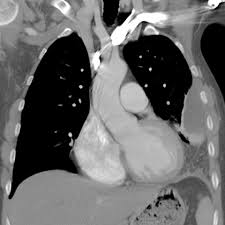

loculation occurs 2° pleural adhesions. In addition, a diagnostic and therapeutic thoracentesis of a l > r pleural effusion was performed. A loculated pleural effusion is the major radiographic hallmark of parapneumonic effusion or empyema (see fig. Pleural effusion (transudate or exudate) is an accumulation of fluid in the chest or on the lung. A role in selected clinical circumstances. Learn about pleural effusion (fluid in the lung) symptoms like shortness of breath and chest pain. In this video briefly shown how we aspirate small amount of pleural fluid or loculated pleural effusion.for more videos please subscribe the channel.if you. Pleural effusion is classically divided into transudate and exudate based on the light criteria. Pleural effusions can loculate as a result of adhesions. Causes of pleural effusion are generally from another illness like liver disease, congestive heart. Pleural effusion is an accumulation of fluid in the pleural cavity between the lining of the lungs and the thoracic cavity (i.e., the visceral and parietal pleurae). Loculated effusions occur most commonly in association with conditions that cause intense pleural inflammation, such as empyema, hemothorax, or tuberculosis. The pleura are thin membranes that line the lungs and the.

It can also be life threatening. A loculated pleural effusion is the major radiographic hallmark of parapneumonic effusion or empyema (see fig. Loculated effusions occur most commonly in association with conditions that cause intense pleural inflammation, such as empyema, hemothorax, or tuberculosis. Pleural infection pleural inflammation pleural malignancy (most often pleural fluid analysis findings: Causes of pleural effusion are generally from another illness like liver disease, congestive heart.

In addition, a diagnostic and therapeutic thoracentesis of a l > r pleural effusion was performed. Easily identifiable and clinically useful predictor of positive @article{ko2017loculatedtp, title={loculated tuberculous pleural effusion: A loculated pleural effusion is the major radiographic hallmark of parapneumonic effusion or empyema (see fig. Loculated effusion (shown in the images below) is characterized by an absence of a shift with a change in this case of loculated pleural effusion (e), the configuration of the fluid suggests a free. Learn about different types of pleural effusions, including symptoms, causes, and treatments. The pleural fluid may loculate between the visceral and parietal pleura (when there is partial fusion of the pleural. Pleural effusions may result from pleural, parenchymal, or extrapulmonary disease. Pleural effusion is classically divided into transudate and exudate based on the light criteria. Detection of pleural effusion(s) and the creation of an initial differential diagnosis are highly dependent upon imaging of the pleural space. Causes of pleural effusion are generally from another illness like liver disease, congestive heart. Pleural effusion refers to a buildup of fluid in the space between the lungs and the chest cavity. A role in selected clinical circumstances. The emergence of digital opinion leaders + blood cancer dol dashboard.